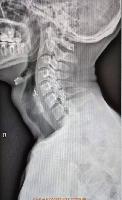

Выезд травматолога-ортопеда, рентгенолога Александра Валерьевича Дидковского.